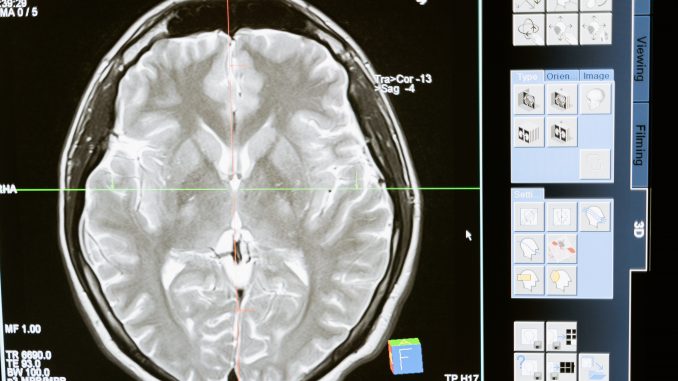

Neuroscientists have been tirelessly working to find effective treatments for brain disorders such as Alzheimer’s and Parkinson’s. However, progress has been slow due to the brain’s complexity and inaccessibility. To address these challenges, the Allen Institute for Brain Science, with support from the National Institutes of Health (NIH) and technology from Amazon Web Services (AWS), is building a groundbreaking Brain Knowledge Platform that aims to synthesize research at a cellular level and revolutionize the understanding and treatment of brain diseases.

The Brain Knowledge Platform will serve as a comprehensive resource, bringing together researchers from 17 institutions worldwide to map the entire brain at a cellular resolution. Led by renowned neuroscientist Ed Lein, this initiative aims to create the largest open-source database of brain cell data, standardizing and compiling massive datasets on the structure and function of mammal brains. By harnessing the power of single-cell genomics, researchers will gain deep insights into the cellular complexity of the brain and the genetic factors influencing cell function.

The ultimate goal of the Brain Knowledge Platform is to provide a foundational resource for neuroscience, similar to the periodic table in chemistry and the human genome map in genomics. By consolidating diverse brain research datasets and enabling cross-species comparisons, the platform will facilitate better diagnosis and treatment of mental and neurological disorders. Through cloud computing technologies offered by AWS, the vast amount of data from billions of brain cells can be stored, analyzed, and accessed by clinicians seeking treatments and cures for brain diseases.